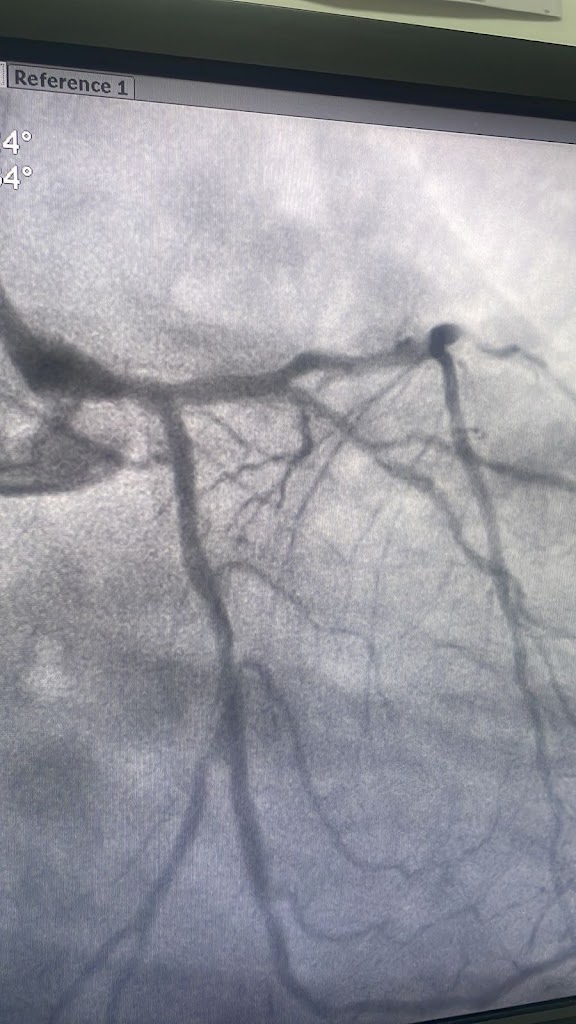

We had an excellent experience with Dr. Anesh Jain. He is an expert cardiologist who performed Angiography, Electrophysiology Study (EPS), and Radiofrequency Ablation (RFA) on my father. Dr. Jain is highly professional, ethical, and easily approachable. He patiently addressed all our questions and provided clear explanations, which greatly reassured us. The entire process from the initial consultation to the post-treatment follow-up was smooth and well-coordinated. I would strongly recommend Dr. Anesh Jain to anyone seeking expert and compassionate cardiac care.

I visited Dr. Anesh's clinic for my mother's treatment.. he diagnosed that my mother was suffering from stable angina and took her in for an angiography which revealed an emergency situation, for which he performed angioplasty immediately and the procedure was real quick hardy 30mins . Thanks to Dr. Anesh for his quick diagnosis and accurate treatment!